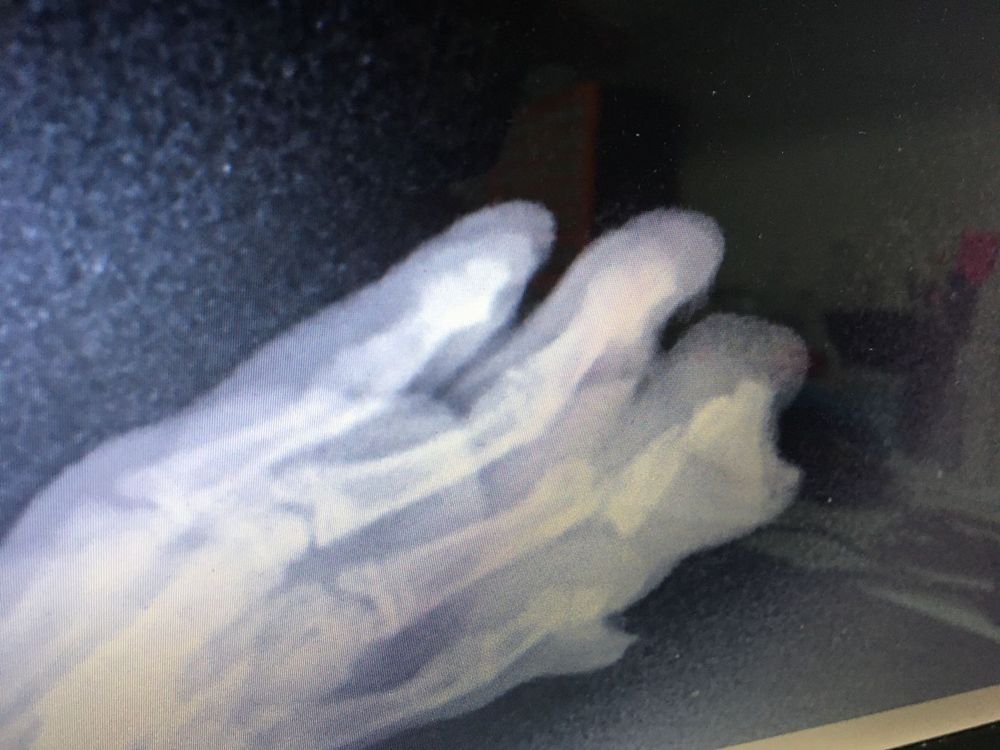

Бедняжечка, скорейшего выздоравления. А почему гипс не наложили, на снимке ведь перелом со смещением?

Наталья, пальчик поставили, как надо, гипс на такой палец не накладывают. Были другие варианты фиксации, но они больше минусов несут, чем плюсов. Сидит в клетке и по дому гуляет на руках